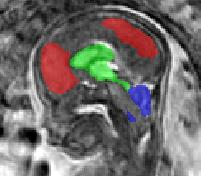

Limiting failures of machine learning systems is of paramount importance for safety-critical applications. In order to improve the robustness of machine learning systems, Distributionally Robust Optimization (DRO) has been proposed as a generalization of Empirical Risk Minimization (ERM). However, its use in deep learning has been severely restricted due to the relative inefficiency of the optimizers available for DRO in comparison to the wide-spread variants of Stochastic Gradient Descent (SGD) optimizers for ERM. We propose SGD with hardness weighted sampling, a principled and efficient optimization method for DRO in machine learning that is particularly suited in the context of deep learning. Similar to a hard example mining strategy in practice, the proposed algorithm is straightforward to implement and computationally as efficient as SGD-based optimizers used for deep learning, requiring minimal overhead computation. In contrast to typical ad hoc hard mining approaches, we prove the convergence of our DRO algorithm for over-parameterized deep learning networks with ReLU activation and a finite number of layers and parameters. Our experiments on fetal brain 3D MRI segmentation and brain tumor segmentation in MRI demonstrate the feasibility and the usefulness of our approach. Using our hardness weighted sampling for training a state-of-the-art deep learning pipeline leads to improved robustness to anatomical variabilities in automatic fetal brain 3D MRI segmentation using deep learning and to improved robustness to the image protocol variations in brain tumor segmentation. Our code is available at https://github.com/LucasFidon/HardnessWeightedSampler.